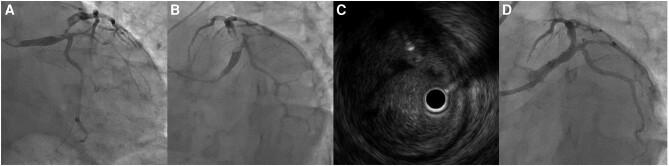

A 37-year-old man without any past medical history presented with chest pain. Electrocardiogram showed ST-segment elevation in leads I, aVL, and V2-V6. Emergent coronary angiography (CAG) showed a 99% stenosis from LMT to proximal left anterior descending artery (LAD). Intra-aortic balloon pumping (IABP) was initiated. Intravascular ultrasound revealed massive thrombus at the culprit lesion. Thrombus aspiration was not enough to reduce the thrombus, thus, we conducted thrombus vaporization with a 0.9 mm ELCA catheter. Coronary angiography after the procedure showed reduced thrombus with thrombolysis in myocardial infarction grade 3 flow. Considering his age and the complexity of stenting the LMT, we completed the procedure without stenting. After the intervention, we initiated triple antithrombotic therapy. On Day 3, we removed the IABP. On Day 11, CAG showed no significant stenosis. Optical coherence tomography revealed ulceration, indicating the presence of plaque disruption at the proximal LAD as the likely cause of thrombosis. With improvement in CAG findings, we stopped heparin and continued dual antiplatelet therapy. He was discharged on Day 20.

一名37岁无既往病史的男性因胸痛就诊。心电图显示I、aVL及V2-V6导联ST段抬高。急诊冠状动脉造影(CAG)显示LMT至左前降支近端(LAD)有99%的狭窄。开始主动脉内球囊泵血(IABP)治疗。血管内超声显示罪犯病变处有大量血栓。血栓抽吸不足以减少血栓,因此,我们使用0.9 mm的ELCA导管进行血栓汽化。术后冠状动脉造影显示血栓减少,心肌梗死溶栓分级为3级血流。考虑到患者年龄及LMT置入支架的复杂性,我们未置入支架完成了手术。干预后,我们开始三联抗栓治疗。第3天,我们撤掉了IABP。第11天,CAG显示无明显狭窄。光学相干断层扫描显示有溃疡形成,提示LAD近端存在斑块破裂,这可能是血栓形成的原因。随着CAG结果改善,我们停用了肝素,继续双联抗血小板治疗。患者于第20天出院。